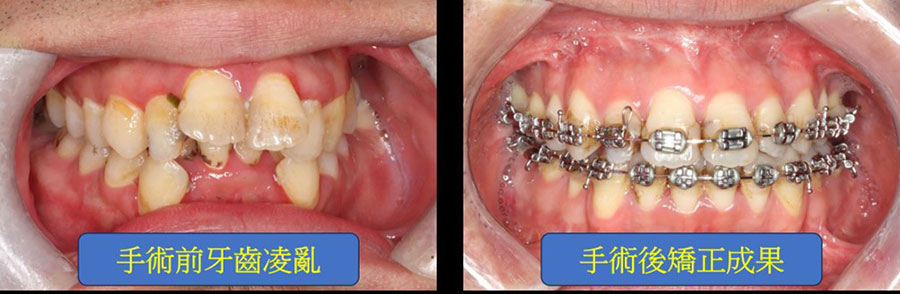

Illustratively, consider the case of Peter (Fig. 1a), afflicted with severe obstructive sleep apnea (AHI: 143; categorized as severe if above 30), possessing a short chin and a protruding upper jaw. Peter underwent tooth extraction and segmented osteotomy of the upper jaw, coupled with advancement and rotation of the lower jaw during surgery (Fig. 1b). This substantially augmented the volume of the oropharyngeal airway, alleviating airway obstruction (post-surgery AHI: 11). Additionally, the chin reshaping resulted in a more aesthetically pleasing facial appearance, bolstering Peter's self-assurance. Post-operative orthodontic treatment enhanced dental alignment, function, and esthetics (Fig. 1c).